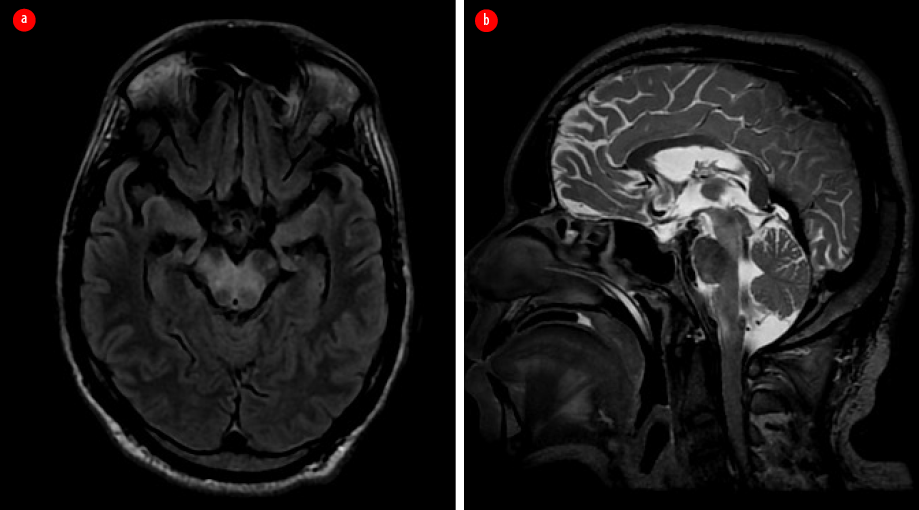

The patient appeared emaciated with a body mass index of 19.8 kg/m2. He was febrile and had right knee joint arthritis. An immediate non-contrast-enhanced magnetic resonance imaging (MRI) brain showed areas of patchy diffusion restriction with corresponding low apparent diffusion coefficient values in the right frontoparietal cortex. Surrounding T2 fluid attenuated inversion recovery hyperintensity suggestive of edema was present in the adjacent white matter with extension to the thalamocapsular region [Figure 1].

Figure 1: Contrast-enhanced MRI of the brain taken on the first visit. (a) Axial diffusion-weighted image shows areas of diffusion restriction in the right frontoparietal cortex. (b) Corresponding apparent diffusion coefficient map indicates the hypointense areas in the involved region. (c) Axial post contrast T1 image shows patchy contrast enhancement in involved area. (d) Axial T2 fluid attenuated inversion recovery image reveals the surrounding edema. (e) Coronal T2 image shows the edema extending to the thalamocapsular region.